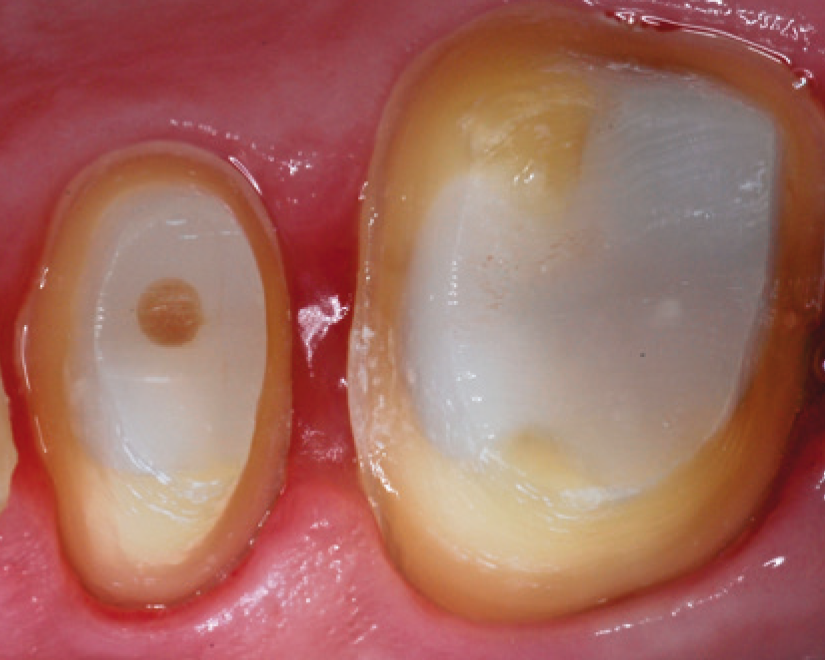

SDR® Plus is optimized for bulk filling posterior cavities that are challenging to access during a dental treatment. Unlike conventional filling materials, it is flowable and can be placed in up to 4 mm increments. This allows dental practitioners to fill a large portion of the posterior cavity in just one step with a flowable material that adapts itself to the cavity walls without further instrumentation. The unique chemistry of SDR® Plus also minimizes shrinkage stress that otherwise could lead to gap formation during light curing.

SDR® Plus is indicated for a variety of dental procedures, including the filling of Class I, II, III and V cavities, pit&fissure sealing, and even core build-ups before placing a crown. It is applied in its flowable state through injection from a syringe, or a small capsule called “Compula Tip”. After placement, SDR® Plus gets light cured by the application of blue light (440 – 480 nm wavelength) from a dental polymerization light. This allows the material to create a dense molecular network and replace the tooth substrate that was drilled away as a permanent restoration.

Start at the bottom of the box, slowly withdraw tip, wipe tip across cusp and allow to self-level for a few seconds. Do not use an instrument to manipulate as this can disturb the self-leveling behavior of the materials.